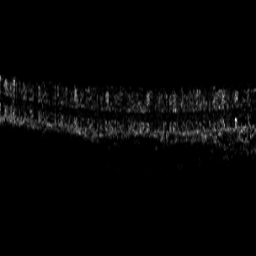

Optical coherence tomography angiography (OCTA) shows its great importance in imaging microvascular networks by providing accurate 3D imaging of blood vessels, but it relies upon specialized sensors and expensive devices. For this reason, previous works show the potential to translate the readily available 3D Optical Coherence Tomography (OCT) images into 3D OCTA images. However, existing OCTA translation methods directly learn the mapping from the OCT domain to the OCTA domain in continuous and infinite space with guidance from only a single view, i.e., the OCTA project map, resulting in suboptimal results. To this end, we propose the multi-view Tri-alignment framework for OCT to OCTA 3D image translation in discrete and finite space, named MuTri. In the first stage, we pre-train two vector-quantized variational auto-encoder (VQ- VAE) by reconstructing 3D OCT and 3D OCTA data, providing semantic prior for subsequent multi-view guidances. In the second stage, our multi-view tri-alignment facilitates another VQVAE model to learn the mapping from the OCT domain to the OCTA domain in discrete and finite space. Specifically, a contrastive-inspired semantic alignment is proposed to maximize the mutual information with the pre-trained models from OCT and OCTA views, to facilitate codebook learning. Meanwhile, a vessel structure alignment is proposed to minimize the structure discrepancy with the pre-trained models from the OCTA project map view, benefiting from learning the detailed vessel structure information. We also collect the first large-scale dataset, namely, OCTA2024, which contains a pair of OCT and OCTA volumes from 846 subjects.